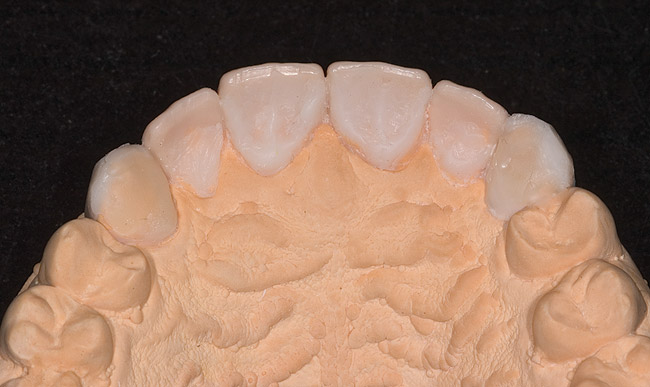

Figure 8  Palatal anatomy restored with wax on stone model.

Figure 8

Stone models were fabricated. The upper model was used to do a wax-up on the palatal/labial surfaces of anteriors (Figure 8), which established the lost form of the teeth and had a stop designed for lower incisors so that non-axial forces would be minimized.